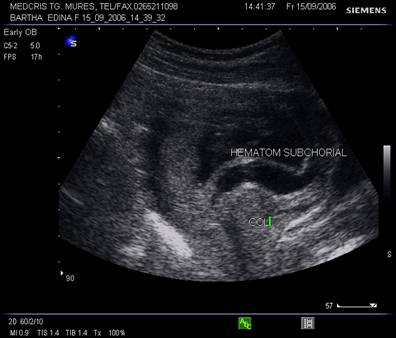

Hematomul

zona hipoecogena intre peretele uterin si chorion, separata de decidua , indica un hematom subchorionic, cateodata mimeaza o sarcina multipla

Prognosticul depinde de marimea hematomului, varsta sarcinii si a mamei. [10]

Localizarea hematomului la nivel corporeal sau fundic uterin, reprezinta dupa Kurjak un factor de prognostic prost. [9]

Benett arata ca hematoamele mari subchoriale, varsta mamei peste 35 ani si sangerarea peste 8 saptamani gestationale, cresc rata avorturilor spontane.[1]

Fig nr. 69. Hematom

subchorial de dimensiune mare, langa orificiul cervical intern (cu sageata)